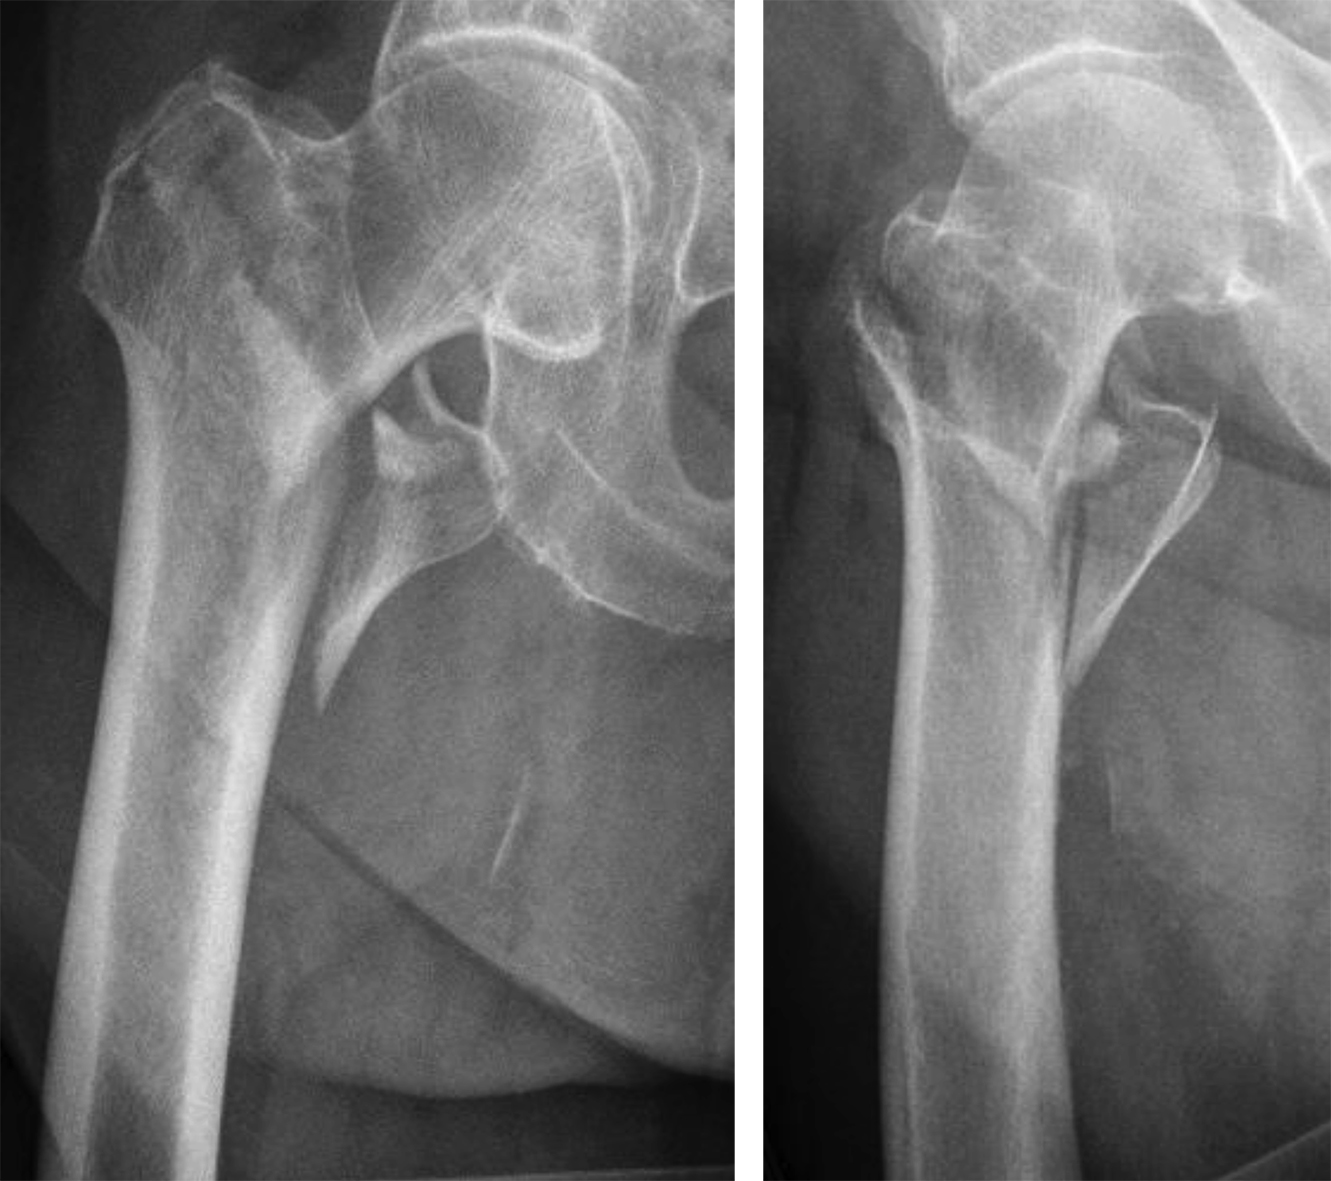

Case 1: Fall at home

An 83-year-old female patient sustained a 31-A.2.2 fracture of the right proximal femur after a fall at home (Figs 1-2). Intraoperative and postoperative images are shown (Figs 3-5).